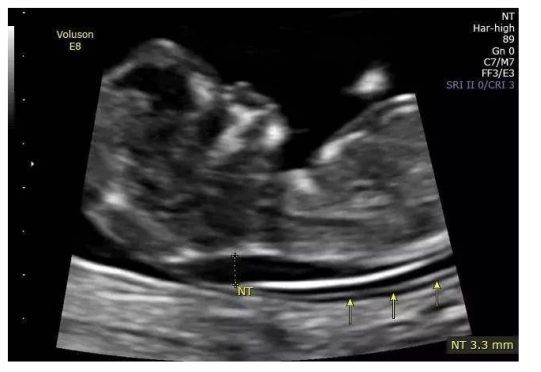

颈项透明层增厚

颈项透明层NT:正常胎儿淋巴系统建立之前,少量淋巴液聚集在颈部淋巴管内形成,妊娠14周以后胎儿淋巴系统发育完善,聚集的淋巴液引流到颈内静脉。

检查时间:妊娠11-13+6周

不同孕周NT正常值是不同的

导致胎儿NT增厚的原因有很多,主要有两大类。第一类是胎儿的染色体异常。这也是最常导致胎儿NT增厚的原因,而其中最重要的有四种的染色体,包括唐氏综合征,也就是21号染色体多了一条,或18.13号染色体体多了一条或者是性染色体的异常。其他的染色体异常也有可能NT增厚,但比例相对来说比较小。第二类是胎儿结构的畸形,如骨骼系统发育的异常,有可能导致NT增厚,相对于染色体异常来说,结构畸形或者其他原因导致NT增厚间的比例比较小,但是我们一定要知道绝大部分NT增厚的孩子是找不到什么原因的,意思就是孩子的染色体是正常的,结构是正常的,NT值随着孕周的增长慢慢丧失,恢复正常。在中孕产科超声的时候,完全就像一个正常的孩子。在这组的孩子里面,他们的预后都是非常好的,他们出生以后发育与早孕时候NT正常的孩子是没有分别的。如NT大于3.5mm染色体有问题的机会越来越大,严重的结构畸形的机会越来越大。

所以我们要是碰见孩子真的有NT增厚的话,我们首先需要排除孩子染色体和结构的畸形。